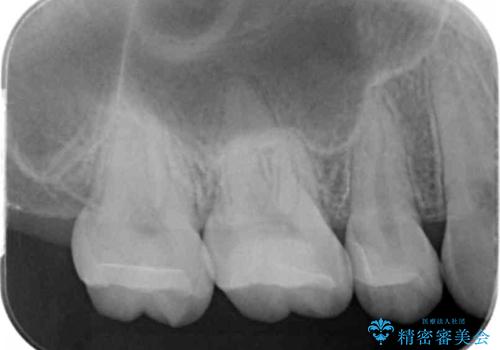

- 奥歯の銀の詰め物を白くしたいとのことで来院されました。

- 右上7 セラミックインレー 77,000円費用は治療当時の料金となります

今回は大きな虫歯もなかったため、1回当たり30分程度の治療時間で計2回の来院回数で治療を終えることができました。